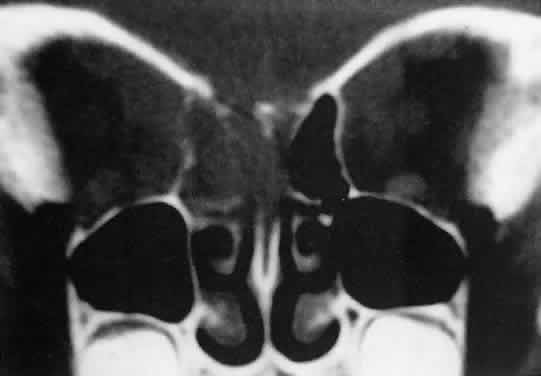

Acute blood cyst formation in this age group makes the distinction between a pre-existent but clinically silent lymphangioma and a rapidly emerging rhabdomyosarcoma a common orbital diagnostic problem. Evidence suggesting an orbitallymphangioma includes the variable finding of conjunctival or eyelid components of the malformation.86 Conjunctival lesions appear as ectatic channels filled with clear or hemorrhagic fluid. Eyelid ecchymosis may result from the seepage of blood out of the thin-walled orbital cysts. Additional developmental anomalies of the eye and adnexa may be present. Other head and neck involvement may be manifest as local hypertrophy (e.g., of the cheek or lips), and cystic palatal lesions may be seen. CT discloses a single or multilobulated mass, which represents only the blood cyst portion of the tumor (Fig. 14). Individual lobules may have different radiodensities depending on the presence of clots or liquefied blood within each cyst (Fig. 15). A generalized increase in orbital dimensions suggests a long-standing, probably congenital process. Echography may help differentiate the cystic components of lymphangioma from cellular rhabdomyosarcoma. Echography shows the blood cysts to be acoustically inactive spaces, with extremely low internal reflectivity (Fig. 16). Clots within the cysts can increase internal heterogeneity, however. MRI has virtually eliminated the need for diagnostic biopsy in this condition, because of its ability to show differing magnetic properties of suspended, degrading blood products (Fig. 17).